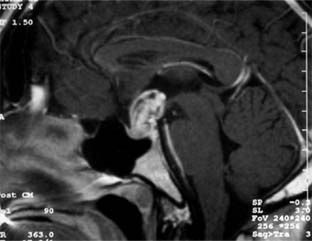

CRANIOPHARYNGIOMA

Craniopharyngiomas are an uncommon group of tumors arising from epithelial remnants of Rathke's pouch (80% of the population normally have such remnants) and characteristically become symptomatic between the ages of 10 and 25 years but occasionally not until the 60s and 70s. They are usually suprasellar (Figure 14-27), occasionally intrasellar. The signs and symptoms vary tremendously with the age of the patient and the exact location of the tumor as well as its rate of growth. When a suprasellar tumor occurs, asymmetric chiasmatic or tract field defects are prominent. Papilledema is more common than in pituitary tumors. Optic nerve hypoplasia can be seen in those tumors presenting in infancy. Pituitary deficiency may result, and involvement of the hypothalamus may cause stunted growth. Calcification of parts of the tumor contributes to a characteristic radiologic appearance, especially in children.

Figure 14-27

Figure 14-27: Sagittal MRI showing contrast enhanced suprasellar craniopharyngioma.